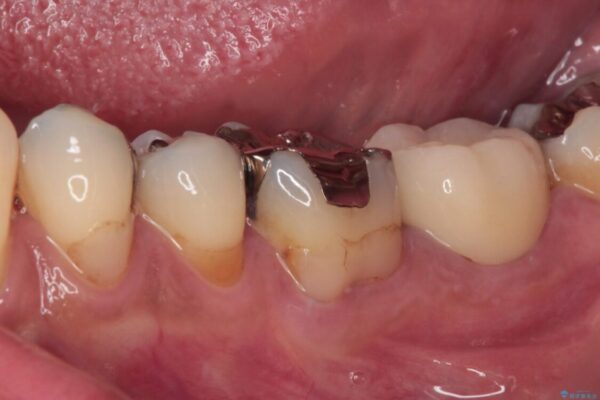

神経組織を部分的に除去することが分かっていたため、ラバーダムなどの環境を整え、無菌的環境下にて処置を進めて行きました。

虫歯は深くまで進行しており、歯冠部の神経から出血が認められました。神経を部分的に除去したところ出血が治まったので、生体親和性の非常に高いセメントにて充填し、仮封をしました。

後日状態を確認したところ、残された神経に異常は認められませんでした。